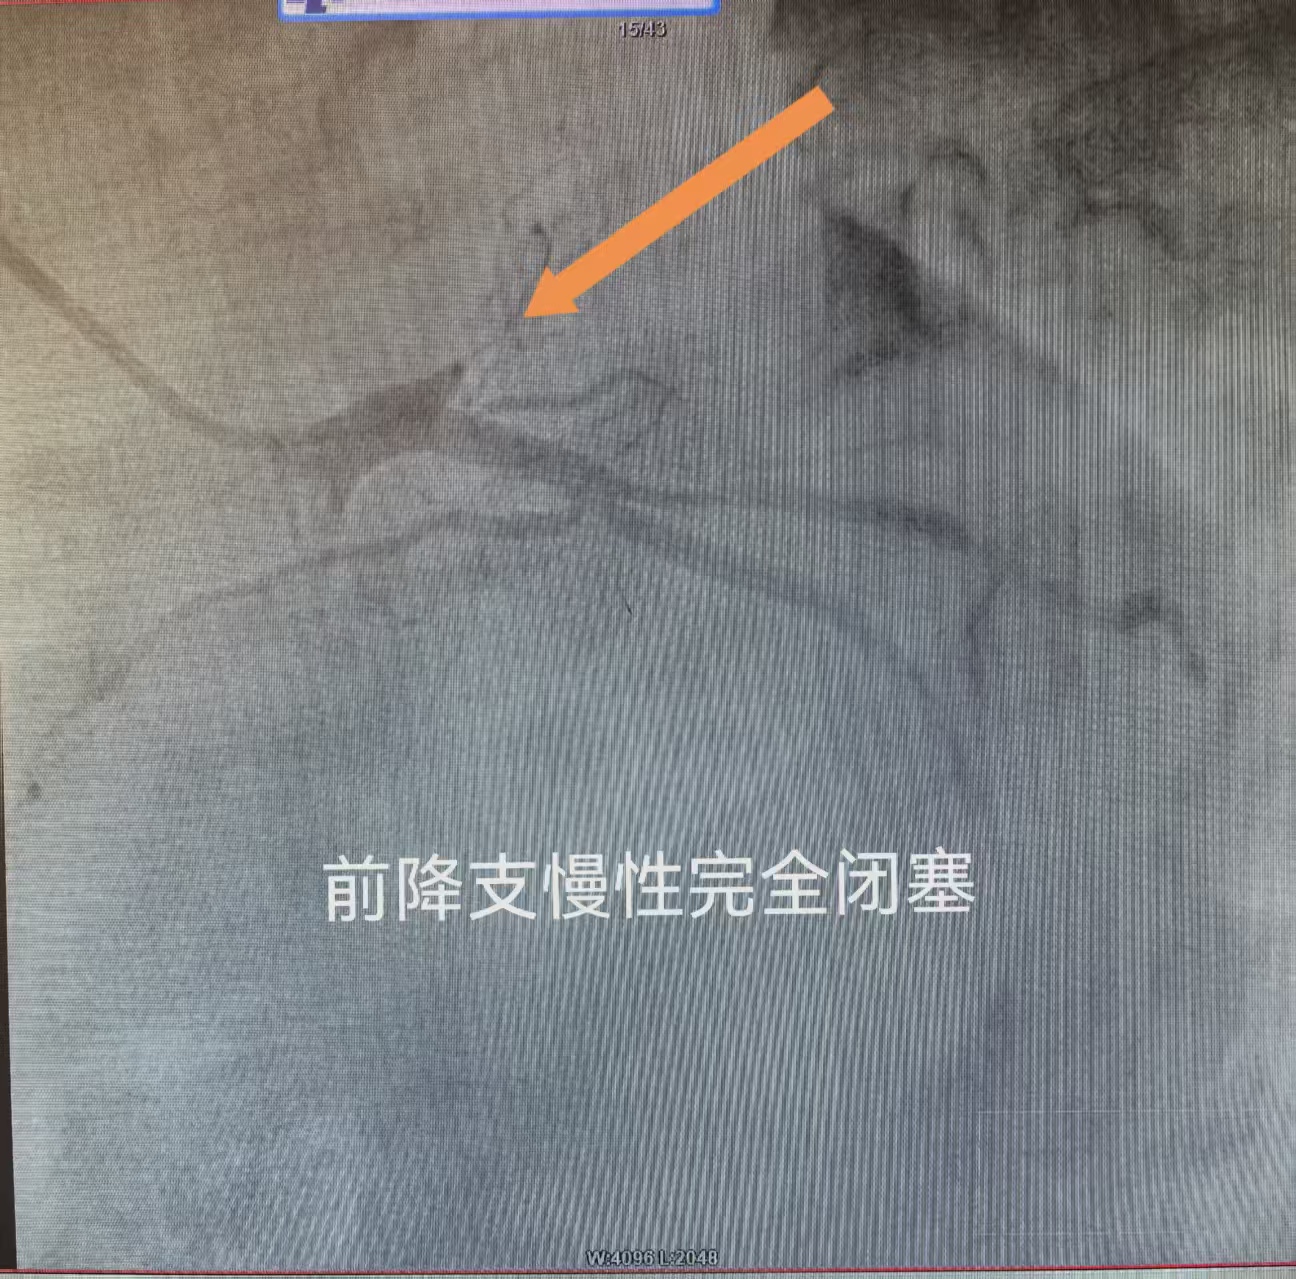

冠脉造影检查精准探明病灶:患者前降支慢性完全闭塞,仅依靠侧支循环勉强供血,右侧冠脉狭窄高达99%,血管内可见明显血栓附着。面对复杂危重的病情,医疗团队综合研判,制定中西医双管齐下的个体化救治方案。急救阶段以西医介入治疗为核心,优先疏通重度狭窄的右侧冠脉,快速恢复心脏主干供血,稳住生命体征;后续结合中医特色疗法,改善全身微循环,实现标本兼顾。